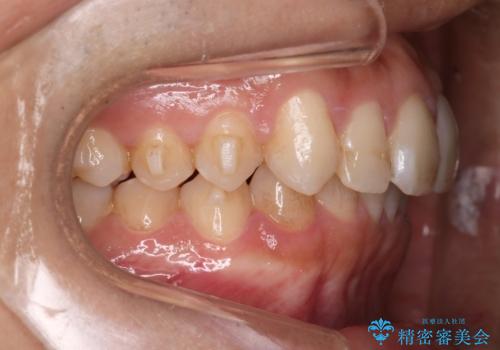

インビザラインにて治療を行うことで、前歯のがたつきが改善されました。

左上1番目の前歯はセラミックをご希望されたので、セラミックにて被せ物の治療を行いました。

とても綺麗な前歯になりました。